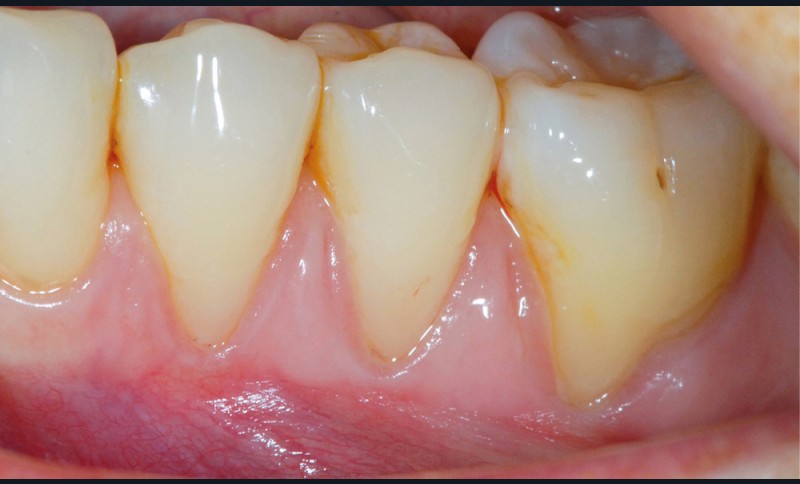

► Il était une fois une amie, médecin, qui présentait des récessions gingivales de 34 à 36. La sensibilité thermique de ces récessions indiquait un recouvrement par une technique de chirurgie plastique parodontale (fig. 1 et 2).

Face aux récessions de classe 1 de Cairo [1] et en présence d’un vestibule relativement profond, une technique de recouvrement radiculaire par lambeau positionné coronairement selon Zucchelli et De Sanctis [2] associé à un greffon conjonctif est choisie.

Cette technique permet de recouvrir des récessions gingivales contiguës par une traction coronaire après une dissection partielle superficielle au-delà de la ligne muco-gingivale. Grâce à un jeu d’incisions des papilles, les incisions de décharge ne sont pas nécessaires. Un greffon conjonctif prélevé au palais selon la technique de l’enveloppe [3] est placé sur les récessions et suturé en même temps que le lambeau par des points suspendus [4].